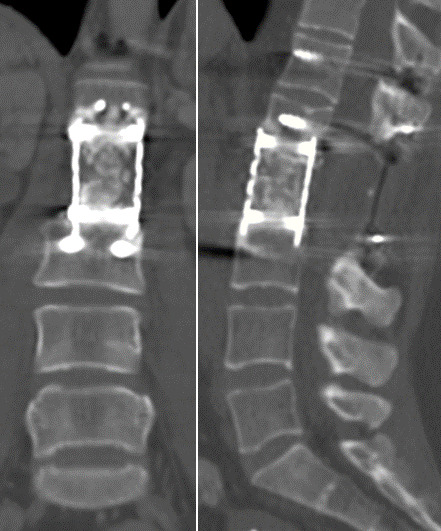

Clinical case: A 40-year-old woman diagnosed with low-grade spinal chondrosarcoma underwent a total en-bloc spondylenctomy (TES) surgery. This technique required a wide resection, anterior reconstruction with a titanium mesh cage (TMC), and posterior stabilization. For several years a favorable clinical outcome was achieved. After 10 years of follow-up, the patient developed acute non-traumatic low back pain without neurological repercussions. The images confirmed a rupture of the titanium cage. After ruling out tumor recurrence, the patient went through spinal instrumentation revision.

Conclusion: Isolated TMC rupture is a rare event scarcely reported in the literature. There is a strong recommendation to instrument two levels proximal and distal to the bone defect in 360° reconstructions after a TES. Stability had likely been lost over the years due to the slow resorption of the bone graft. We consider necessary studies with a higher casuistry and level of evidence to analyze the contributing factors for the event of TMC rupture.